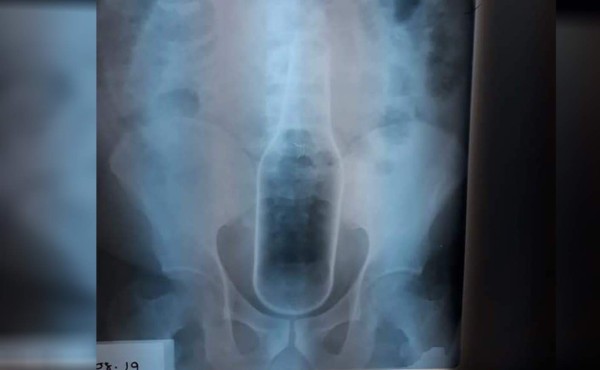

Un equipo de médicos le extrajeron la botella tras practicarle una cirugía.

Un hondureño fue operado de emergencias en el Hospital Regional del Sur en Choluteca luego que se metiera una botella de cerveza en el ano.

Médicos especialistas le extrajeron la botella tras practicarle una cirugía y ahora se encuentra interno mientas se recupera establemente.

'El paciente padece de problemas de hemorroides y estaba haciendo la introdución de esta botella, se la introdujo toda y no pudo sacarla', explicó un doctor del hospital público donde fue atendido.

'Tuvo que hacerse intervención quirúrgica, una laparotomía para extraer el cuerpo extraño', indicó.